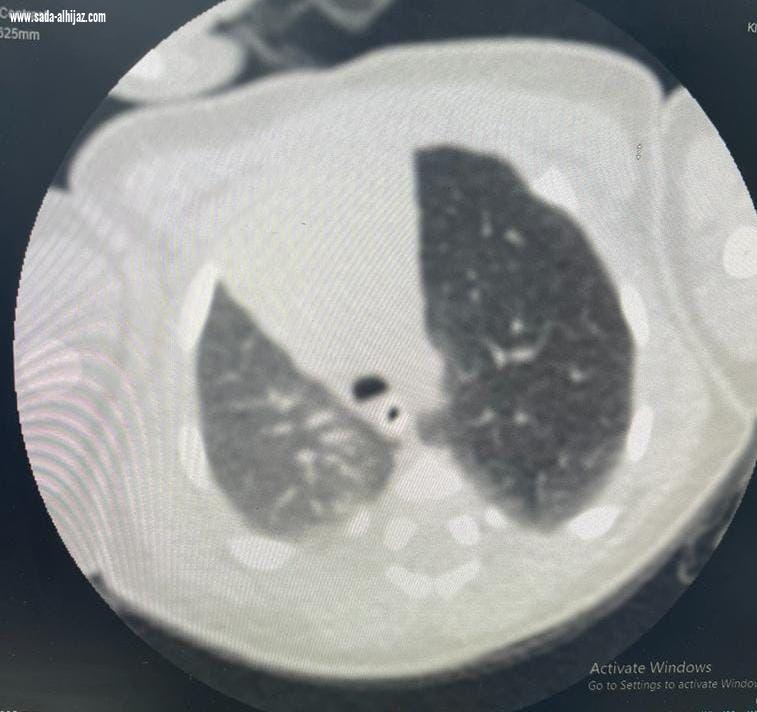

إستقبل مجمع الملك فيصل الطبي بالطائف حالة طفل خديج حديث الولادة يعاني من صعوبة في التنفس، وتم بشكلٍ عاجل عمل فحوصات وتحاليل وأشعة دقيقة للطفل أثبتت وجود تمدد بالفص الأيسر العلوي من الرئة، وتم تشكيل فريق طبي من عدة تخصصات شملت أطباء جراحة الصدر، وأطباء الرعاية الفائقة للأطفال الخُدج بالمجمع، وبعد دراسة الحالة تم اتخاذ قرار بإجراء جراحة عاجلة ودقيقة لاستئصال الفص الأيسر العلوي من الرئة عن طريق شق صدري محدود بمشاركة الدكتور نادر البرعي استشاري جراحة الصدر، والدكتور جاسر علي استشاري جراحة الصدر، والدكتورة عبير أحمد عبد السلام حسن طبيبة حديثي الولادة.

ووفقاً لما ذكرهُ متحدث صحة الطائف سراج الحميدان لـ "سبق"، فقد استغرقت الجراحة ساعتين وتحسنت الحالة الصحية للطفل بشكلٍ ملحوظ، وخرج المريض من المستشفى بعد أيام من العملية بدون مضاعفات بفضل الله.